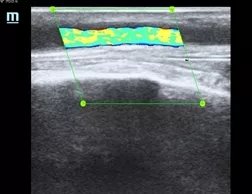

该患者为男性,规律血液透析,因内瘘流量不足,静脉压力高就诊,血管超声提示头静脉距离吻合口8-10cm处狭窄约70%,血流速度明显增快,节段性狭窄明确,符合球囊扩张成形术指征,同张愚主任讨论病情后,决定实施超声引导下经皮动静脉内瘘狭窄球囊扩张成形术。术后头静脉内径恢复正常,当日出院,第二日即应用内瘘进行血液透析,流量稳定,静脉压降至正常。

扩张后